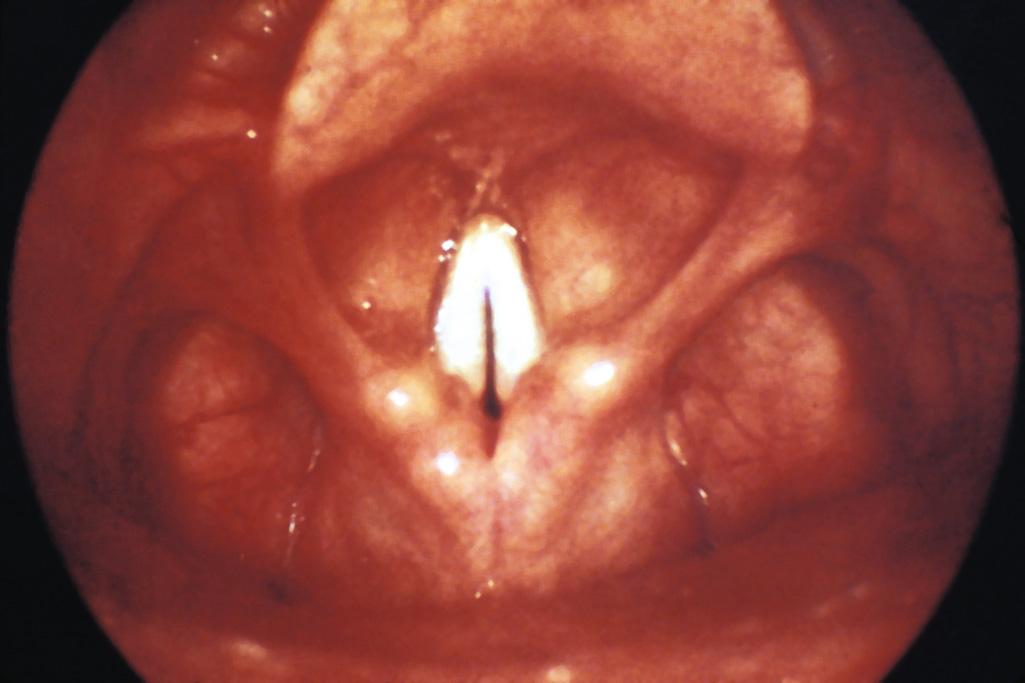

Once the patient is anesthetized, repeat the steps described earlier and position the mirror against the soft palate. Rotate the angle of the mirror and systematically inspect the base of the tongue, valleculae, epiglottis, piriform recess, arytenoids, false and true vocal cords, and if possible, the superior aspect of the trachea (see Fig. 63.2 , plate 6 ). Observe for masses, evidence of infection, asymmetry, or FBs. Further evaluate the anterior structure of the larynx and function of the vocal cords by having the patient say “eeee” in a high-pitched voice. This should move the epiglottis away from blocking the view of the larynx and bring the true cords together at the midline ( Fig. 63.5 ).

Figure 63.5, Instruct the patient to say “eeeeee” in a high-pitched voice during the examination. This lifts the epiglottis out of your field of view and allows excellent visualization of the glottis. In this picture the vocal cords close with phonation. A paralyzed cord is easily discerned from one that is normal.